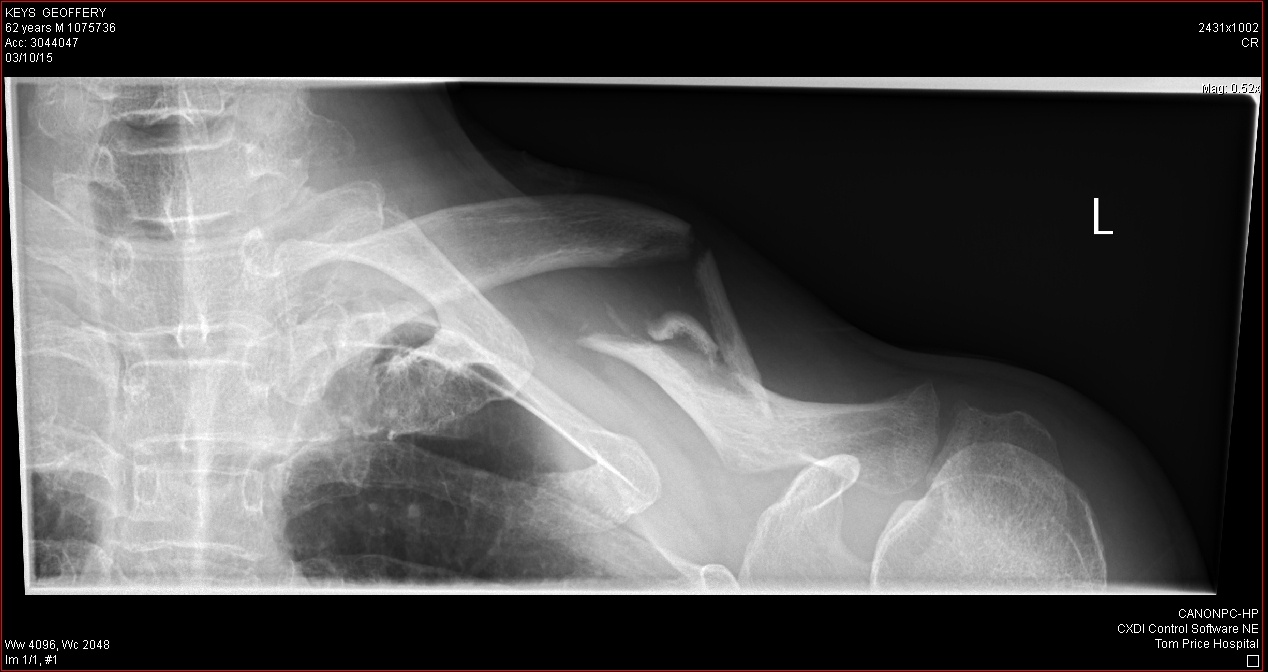

I set off along the track once more, riding steadily at a reduced speed of 40-50kph and trying to stick to the chicken track at the edge. All was well until after about 10kms the front wheel dug into some gravel and I was spat off the bike. This time I landed really badly and as I moved to straighten myself out I realised I had broken my collar bone. I knew the feeling as I had broken the right one about seven years ago. Now I had a matched pair. I didn’t bother trying to get up. It’s a busy track and I knew someone would be along soon to help me. I was right and within a minute or two a couple of fourbys arrived. Some guys picked up my bike and moved it off the track and a family put me in the back of theirs to take me on to the Eco Resort. They were good enough to bring the bags off the back of my bike too. I knew that I’d gone down really hard that time because the straps holding the bags onto the bike had snapped, something that had not happened before. If you’re familiar with ROK Straps you’ll know this is very hard to do.

Being a mining town, Tom Price has a small hospital and they processed me efficiently, if slowly. Eventually the on-call radiologist arrived and I was duly x-rayed. Broken collar bone confirmed and the doctor said it would need pinning. Looking at them I was inclined to agree. It looked a mess. I was given a room to myself where I was able to get a very much needed shower and some food. I had been given a disc with the x-rays on it, in case I wanted to receive some of my treatment in another state.